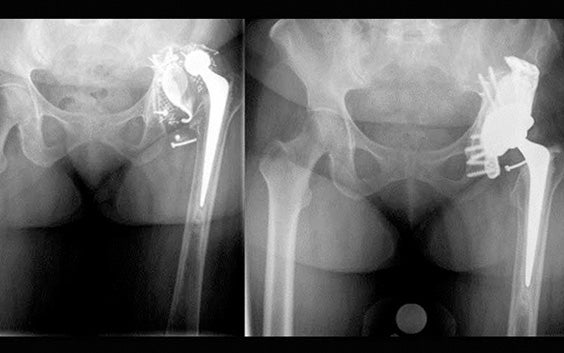

Fixation et stabilité à long terme optimisées

Les implants aMace sont conçus pour optimiser la fixation avec des axes de vissage croisés. Le renfort intégré reproduit les caractéristiques osseuses et est conçu pour améliorer la fixation secondaire lors de la croissance osseuse interne.

Guides de perçage brevetés

Des guides imprimés en 3D innovants vous permettent d'optimiser la fixation primaire en positionnant les vis croisées nécessaires comme indiqué sur le plan préopératoire.